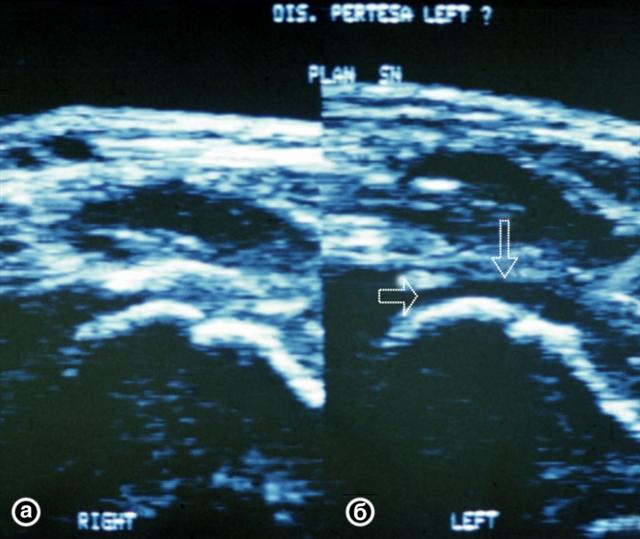

Рис. 22. Ультрасонограммы тазобедренных суставов ребенка 5 лет в норме (а) и при болезни Пертеса в ранней ее стадии (б): контур головки бедренной кости не изменен, в полости тазобедренного сустава определяется скопление жидкости (указано стрелками).